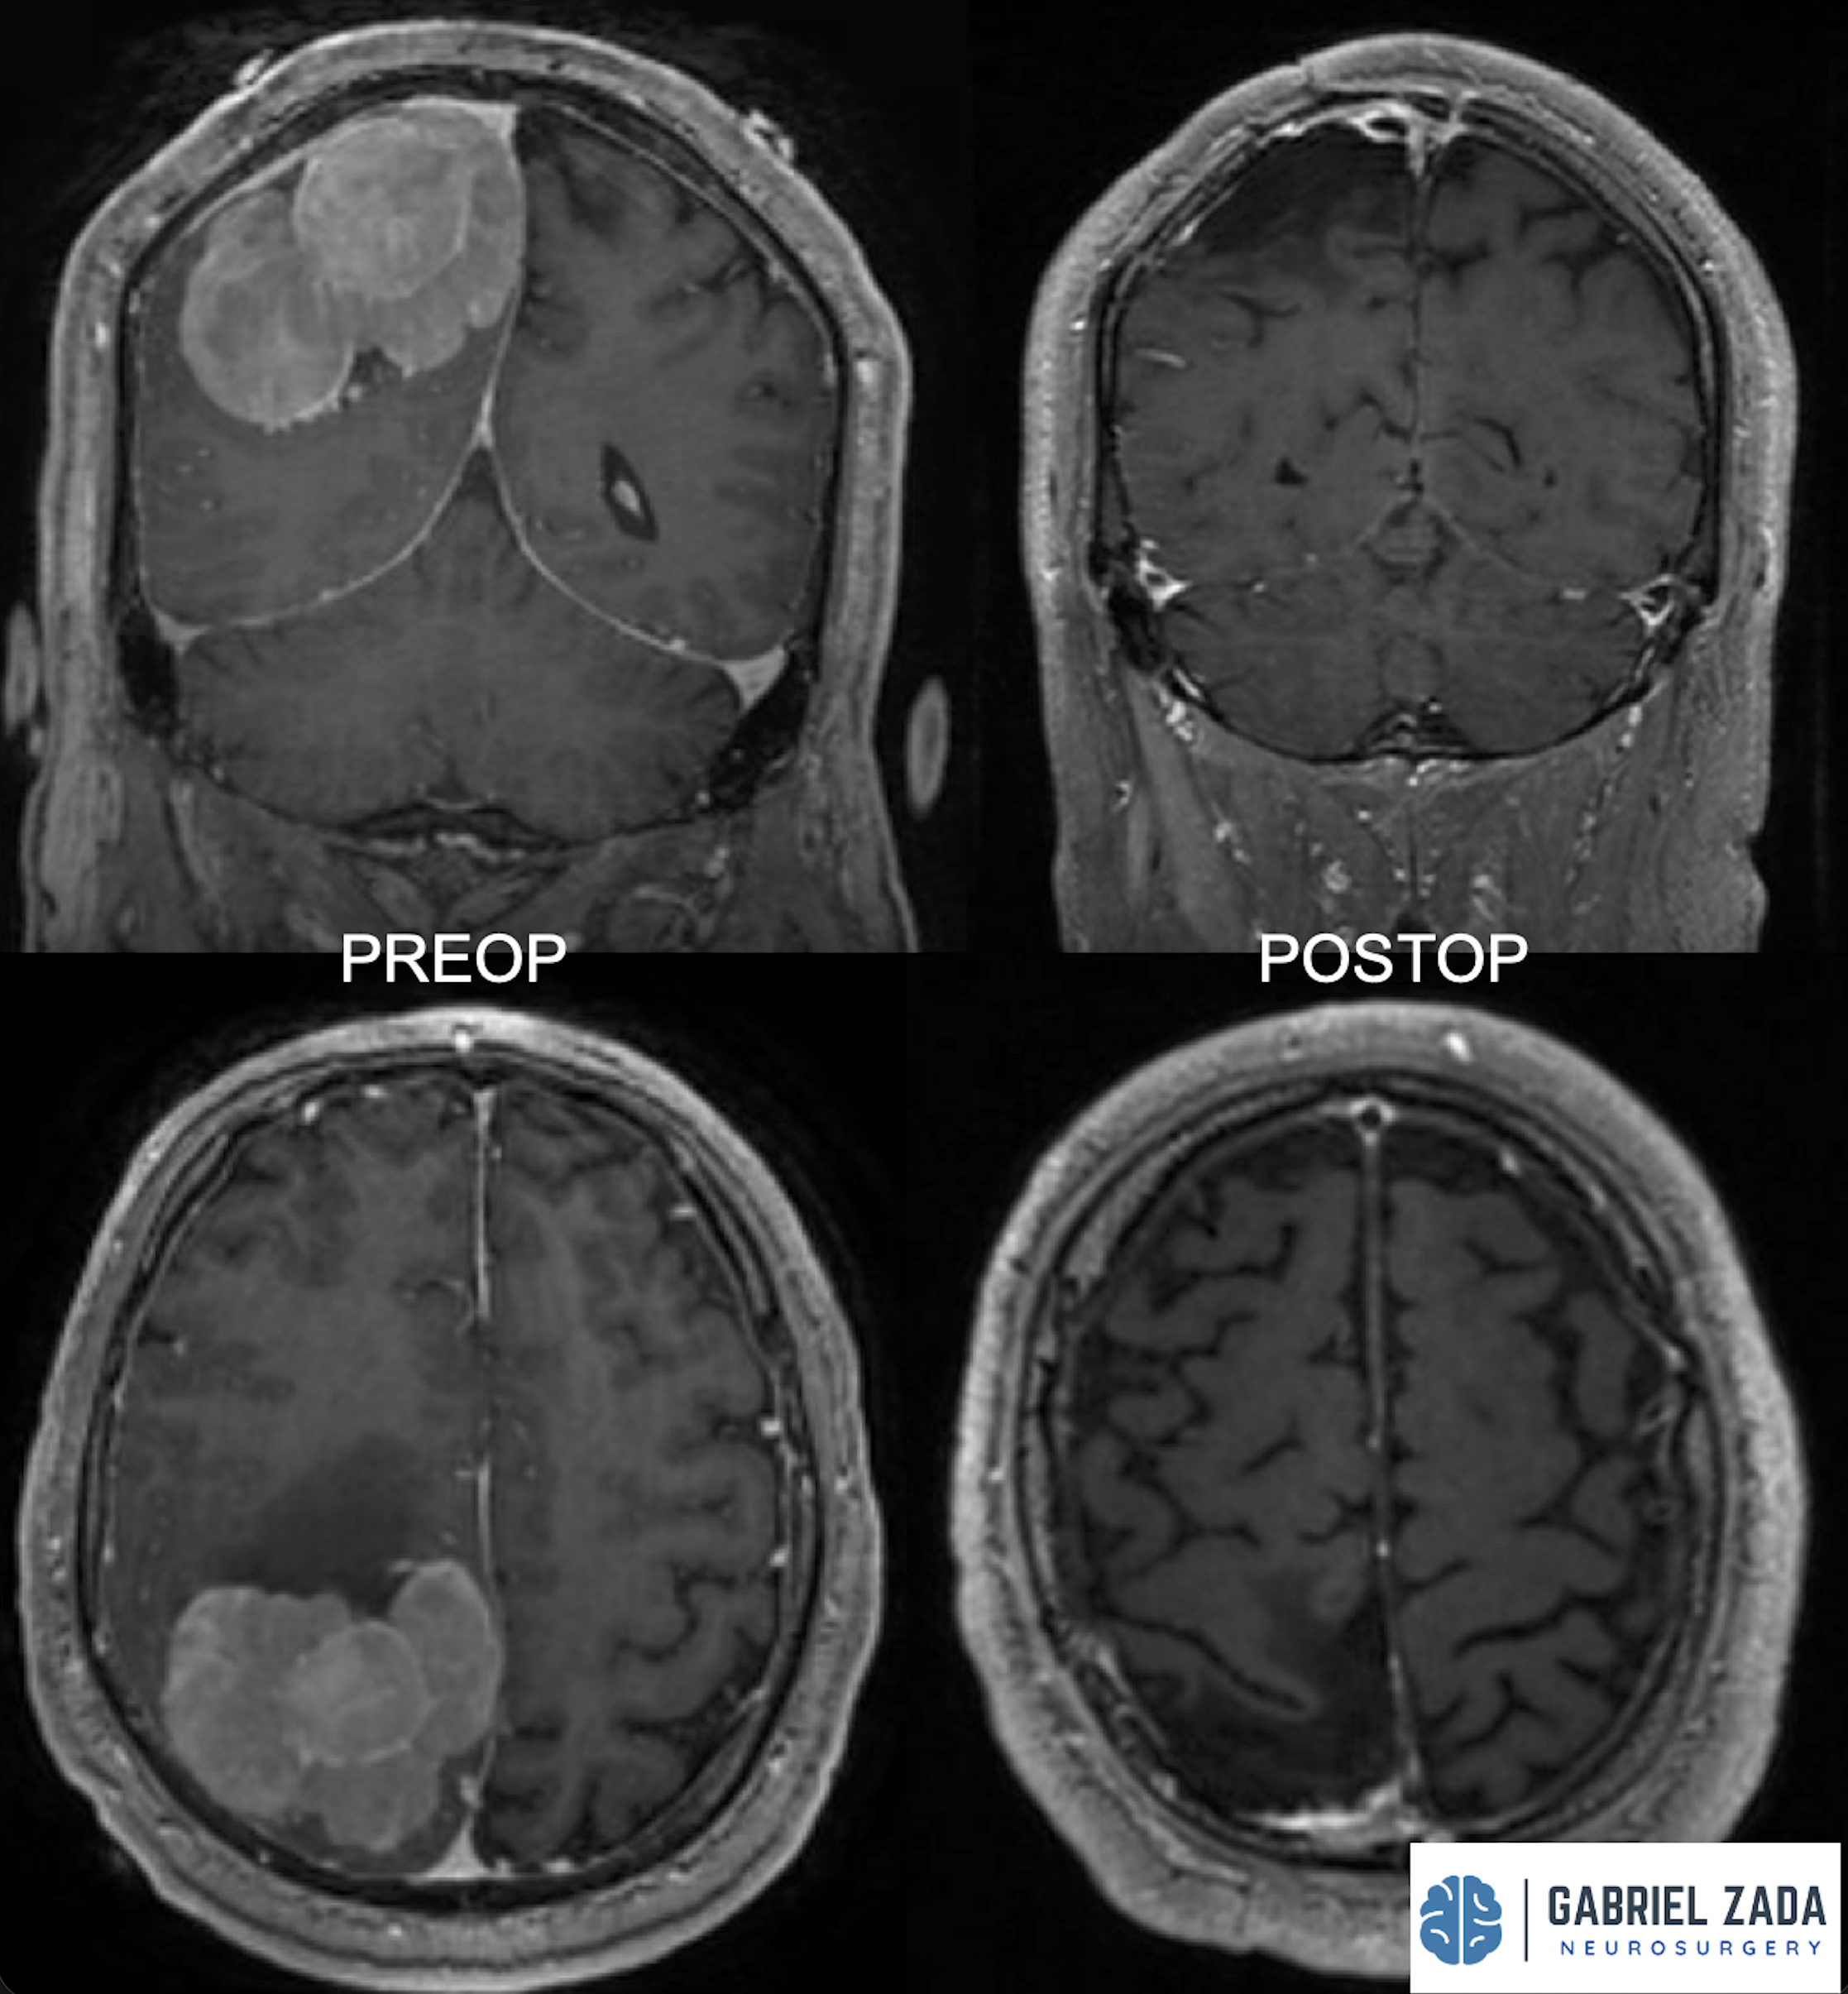

Explore this comprehensive gallery featuring pre‑ and post‑operative imaging of patients with skull‑base tumors treated by Gabriel Zada, MD, MS, FAANS, FACS. These cases highlight Dr. Zada’s expertise in advanced neurosurgical techniques and outcomes.

*Representative cases shown for educational purposes. All images de-identified. Individual results vary.